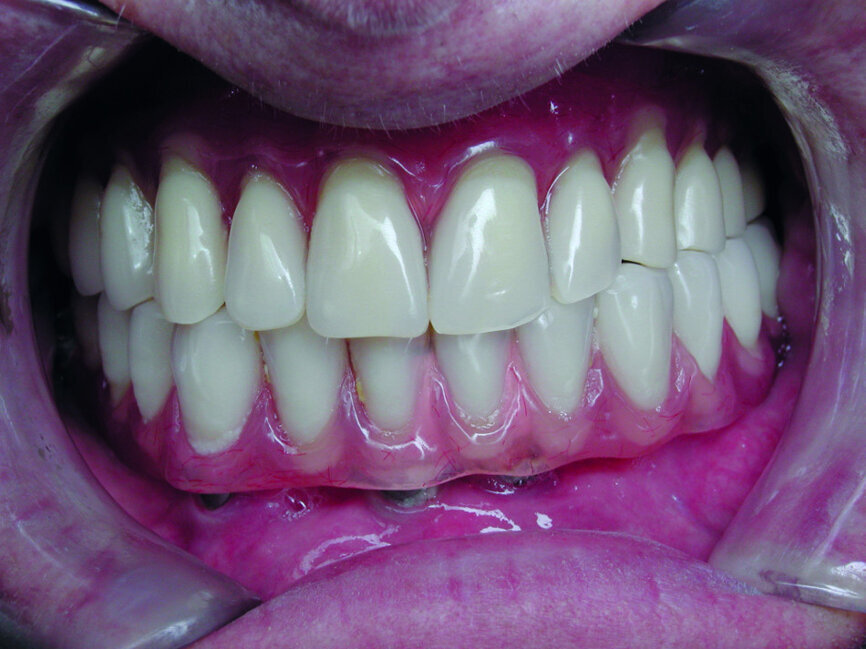

Cas 2c : prothèses en bouche